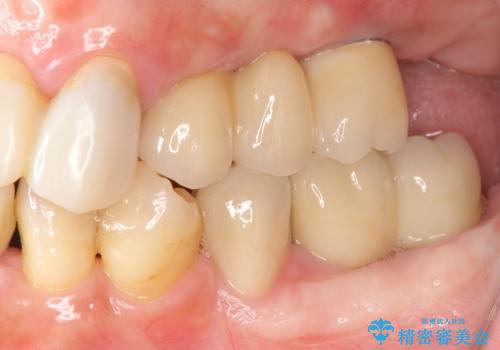

歯周病 全顎治療

- 前歯の見た目、入れ歯による噛めないことの改善を求めて来院されました。

検査により全顎的な歯周病治療、欠損のインプラント補綴、根管治療が必要な状態であることをお伝えし、治療を計画します。

失ってしまった機能を回復し、今後歯を失わないよう残せる歯に歯周病治療を行い、安定した咬合を確立することで長期的に問題なく噛めるような口腔内環境を達成できるようになると考えます。